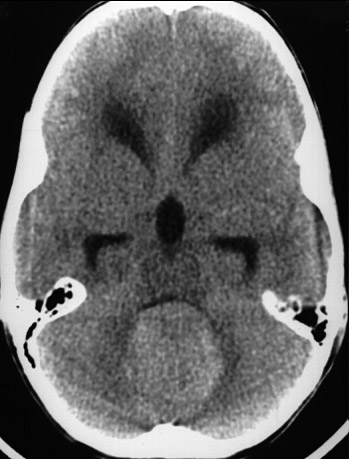

On CT scan, there is a midline cerebellar mass in a child. This is a medulloblastoma. Medulloblastoma is one form of primitive neuroectodermal tumor (PNET), just as a neuroblastoma is.